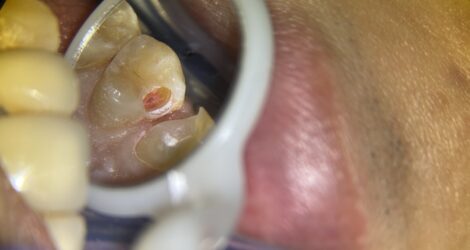

古い詰め物が歯と歯の間にあり、フロスを通すと引っかかって気になるとのことで、詰め物を削ったら中が虫歯になっていました💦(ピンク色に染まっている所が虫歯です😈)

虫歯を取っていくと神経が露出するギリギリのところでした。